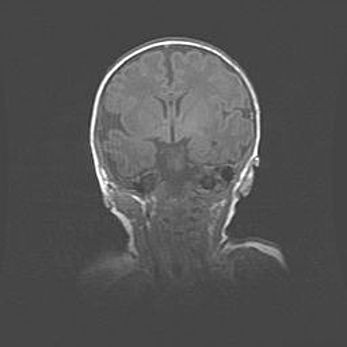

Открытая гидроцефалия.

Возраст: 9 месяцев 12 дней

Вес: 6800 г

Пол: мужской

Окружность головы: 41,5 см

Срок гестации: 28 недель

Гидроцефалия головного мозга у новорожденных имеет характерный признак: опережающий рост окружности головы приводит к визуально хорошо определяемой гидроцефальной форме сильно увеличенного в объёме черепа. Детские неврологи определяют следующие симптомы гидроцефалии у грудничков: выбухающий напряжённый родничок, частое запрокидывание головы, смещение глазных яблок к низу.